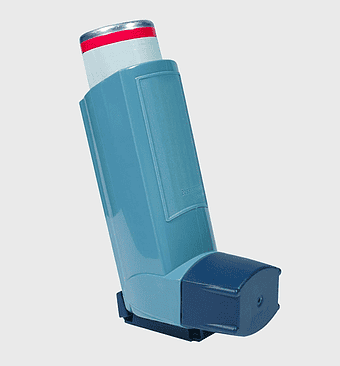

Albuterol inhaler, asthma treatment device, levosalbutamol medication, chronic obstructive pulmonary disease relief, respiratory aid tool, medical inhalation device, portable asthma solution -